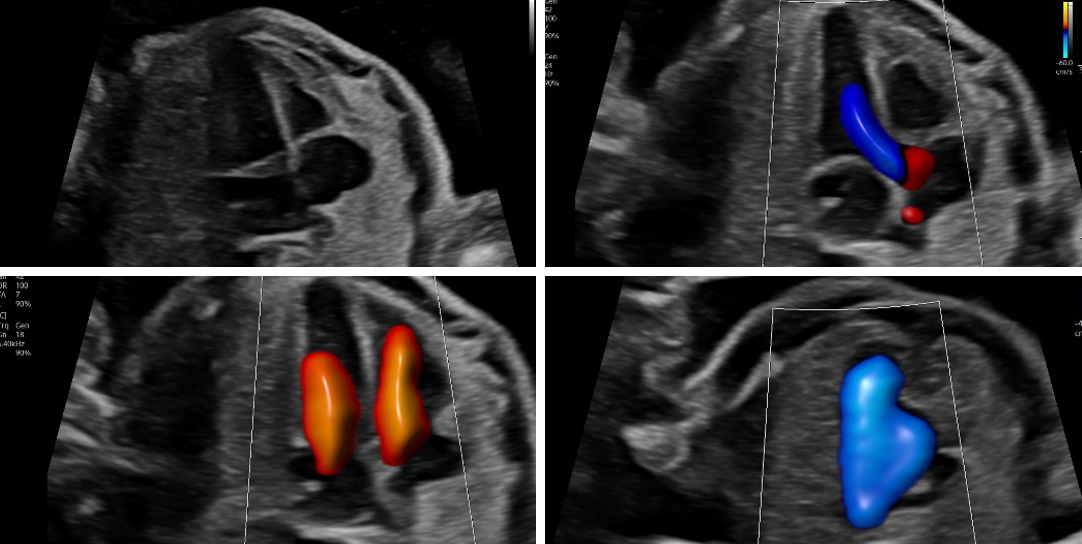

Doppler

Bei dieser Untersuchung messen wir die Durchblutung in der Nabelschnur und anderen Blutgefäßen, um die Versorgung Ihres Kindes zuverlässig einzuschätzen und zu überwachen. Je nach Fragestellung ist diese Untersuchung ab 11 SSW möglich.